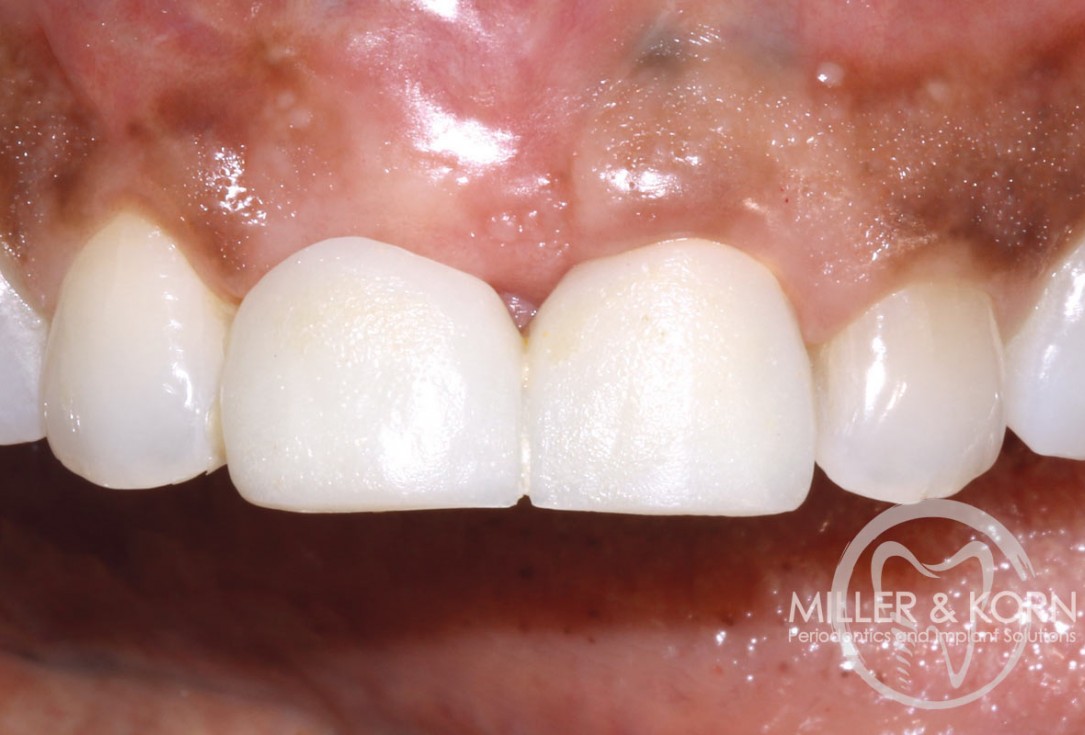

20/22 - Smile one-week post insertion of final prosthesisImmediate implant placement and regeneration of ridge using an allograft bone ring and Jason® membrane - Drs. Miller and Korn